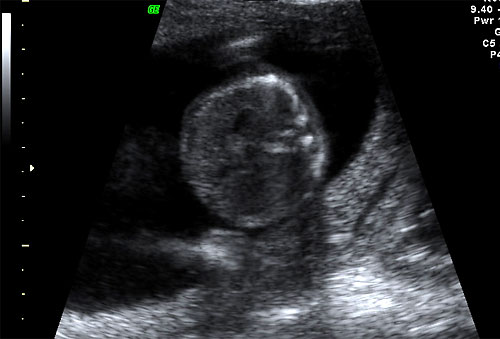

Normal BPD and HC at 16 weeks |